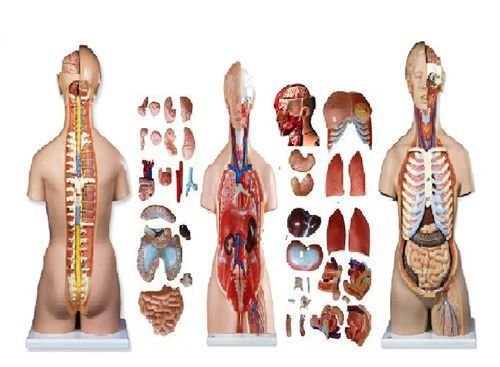

HUMAN TORSO UNISEX 85 Healthcare,Life Science Medical Lab Teaching & Education

4D PREGNANCY TORSO Human Body Pregnant Anatomy 3D Model Organs science Medical